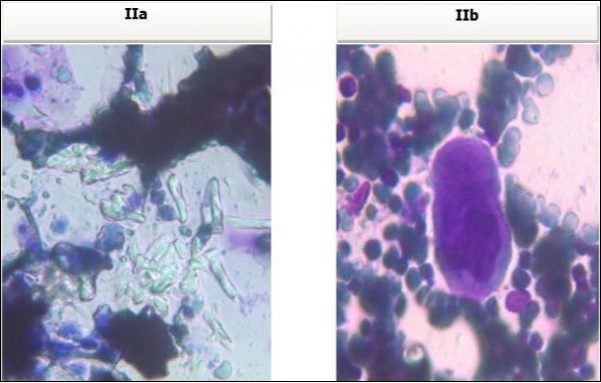

A 30 years old male, resident of Lahore was admitted for opinion regarding the necessity for regular hemodialysis after rejection of second renal transplant. Family history was suggestive of hereditary disease as two of his sisters had died of nephrocalcinosis leading to chronic renal failure at the age of 4 years. Consanguineous marriages in past many generations were also reported. Three cousins of the patient had recurrent stones with normal kidney functions. His past history revealed retention of urine at the age of 5 years due to stone in urethra. Patient presented again after 20 years in 2008 with retention of urine which was relieved by catheterization. Renal ultrasound and X ray KUB reported normal kidneys in both instances. Work up for stone formation was not undertaken at that time. The patient was put on hemodialysis and was planned for transplant which was undertaken in May 2009. After one month, follow up tests revealed Serum Creatinine to be 2.0 mg/dL. Renal Biopsy done in Sep 2009 revealed rejection of transplant. Hemodialysis was started and a second transplant was contemplated. Hemodialysis continued for 2 years till Dec 2011 when second transplant was carried out. A repeat renal biopsy was indicated for increasing serum creatinine. Again transplant rejection was evident on histology. Further investigations revealed Urinary oxalate excretion exceeding 40 mg/day (30 mg Oxalate/gram creatinine). His Blood investigations at the time bone marrow studies revealed bicytopenia with a Haemoglobin of 7.8g/dl, White blood cell count of 5.8 x 109/l; Platelet count of 120 x 109/l. Serum Creatinine was 3.6mg/dl. An attempt to correct the cytopenias by iron, vitamin B12 and folic acid supplements met with failure. No response to anemia could be elicited by adding erythropoietin to the treatment regimen. Renal and bone marrow biopsy were undertaken. Renal biopsy of the patient revealed crystals of calcium oxalate in the tubules (Figure 1). The same crystals were also visualized in bone marrow aspirate (Figure 2a and Figure 2b) and trephine biopsy (Figure 3).

Figure 2a & b.Photomicrograph of bone marrow aspirate from case I revealing oxalate crystals interspersed in the bone marrow fragments and a foreign body giant cell.